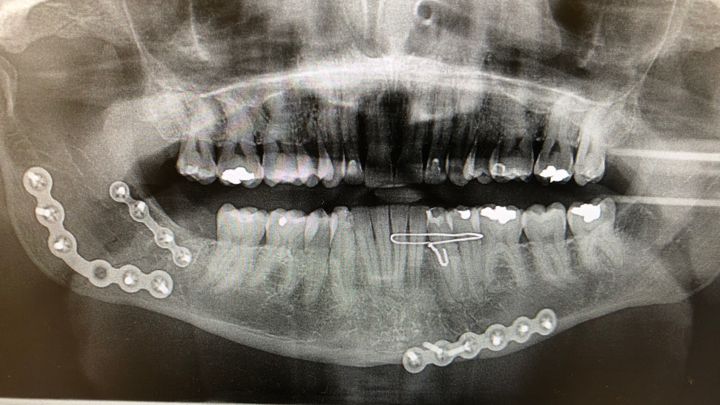

Late on November 23, 2020 when getting off the train he was attacked by 3 assailants and taken to Cook County Hospital in critical condition. His lower jaw was separated in 2 places causing extensive damage to his teeth and destroying the permanent retainer on his lower teeth. Also his nose was broken, major damage to his right eye socket, multiple cuts requiring stitches, and was concussed.

Three days later he had Oral Surgery to insert plates and screws to reconnect the lower jaw, remove a wisdom tooth and the permanent retainer. A second surgery the same day to repair his broken nose and stitch up the multiple cuts on his face from the attack. Surgeries were 5 hours combined with 4 more hours of recovery. After release he was given some vocal and other exercises to help prevent scarring and permanent limitation of his jaw. He was also advised to get a care provider for the 5 days post surgery.

Steve is now facing multiple root canals and crowns due to the separation in his jaw. Loss of the permanent retainer and wisdom tooth has also cause shifting of his lower teeth.